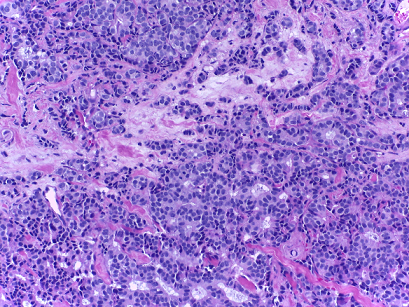

Fig. 6(a) depicts, for the top-10 participants, the difference between the reported performances on the training set (cross-validation) and the achieved performances on the hidden test set. Also, a class-wise study of these methods shows that the Benign and In situ classes are the most challenging to classify (Fig. 6(b)). In particular, Fig. 6(c) and 6(d) show two images with 100% inter-observer agreement that were misclassified by the majority (at least 80%) of the top-10 approaches.

Refer to caption

(c) Case of Benign mostly misclassified as In situ

(d) Case of Benign mostly misclassified as Invasive

(e) Example of an In situ case from the training set

(f) Example of an Invasive case from the training set

Fig. 6: Examples of images misclassified by the top-10 methods of Part A and similar examples in the training set.

Despite their high accuracy, the submitted methods still failed on correctly predicting images of the more subtle Benign and In situ classes. In fact, Fig. 5b shows that the Benign class is the one that affects the most the performance of the methods, which is to be expected since the presence of normal elements and usual preservation of tissue architecture associated with benign lesions makes this class specially hard to distinguish from normal tissue. Furthermore, the Benign class is the one that presents greater morphological variability and thus discriminant features are more difficult to learn.

The generalization capacity of the methods is also affected by the image acquisition pipeline. Specifically, during the acquisition of field images, pathologists focus on capturing regions that contain representative features (tissue architecture, cytological features, etc.) for the given label. As a consequence, whenever those features are subtle, as it is common on normal tissue, specialists tend to capture non-relevant structures, such as fat cells. Likewise, for in situ carcinomas it is common to center the images on mammary ducts, where the cancer is contained. Fig. 6(c) and Fig. 6(e) show two images from the test and training sets, respectively. Fig. 6(e), labeled as In situ, is centered on a duct and surrounded on the left by non-relevant fat tissue. Fig. 6(c) has, by coincidence, the same acquisition scheme of Fig. 6(e) and despite being correctly classified as Benign by 100% of the experts, 60% of the top-10 methods classified it as In situ and 10% as Normal. Likewise, Fig. 6(d) shows a full-consensus Benign test image that was classified by 70% of the top-10 as Invasive. Once again, this image has a similar overall tissue organization as training cases of other classes, as shown in the invasive tissue depicted in Fig. 6(f). The differences, which lie in the cytological features (nuclei size, color and variability), are clear and yet the approaches failed to correctly capture these discriminant characteristics. This suggests that the networks may be partially modeling how images were acquired instead of focusing on what leads to the classification [1].